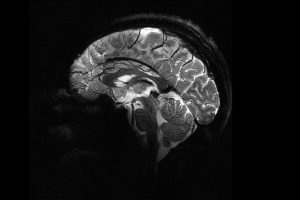

نشرت هيئة الطاقة الذريّة في فرنسا صورة هي الأدق على الإطلاق لدماغ إنسان بعد تلقيهم الضوء الأخضر لاستخدام أقوى جهاز تصوير بالرنين المغناطيسي. وكانت السلطات المعنية قد تمهلت في منح التصريح بعد أن استُخدم الجهاز لأوّل مرة عام 2021 لتصوير ثمار اليقطين، ولكن خلال الأشهر القليلة الماضية تقدم نحو 20…